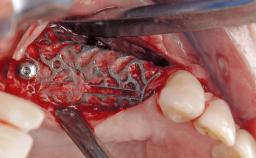

In this case, Myroslav Solonko, Ignacio Sanz Sánchez and Mariano Sanz present a treatment that aims to eliminate exposed implant threads by modifying the implant surface, converting a moderately-rough surface into a smooth surface.

A 63-year-old male patient was referred to the post-graduate periodontal clinic of the Complutense University of Madrid for the treatment of peri-implantitis. According to the patient’s record, all his maxillary teeth had been extracted ten years previously due to severe periodontitis, and a full-mouth implant-supported restoration on eight implants was placed. No supportive periodontal therapy was provided apart from occasional check-ups by the restorative dentist.